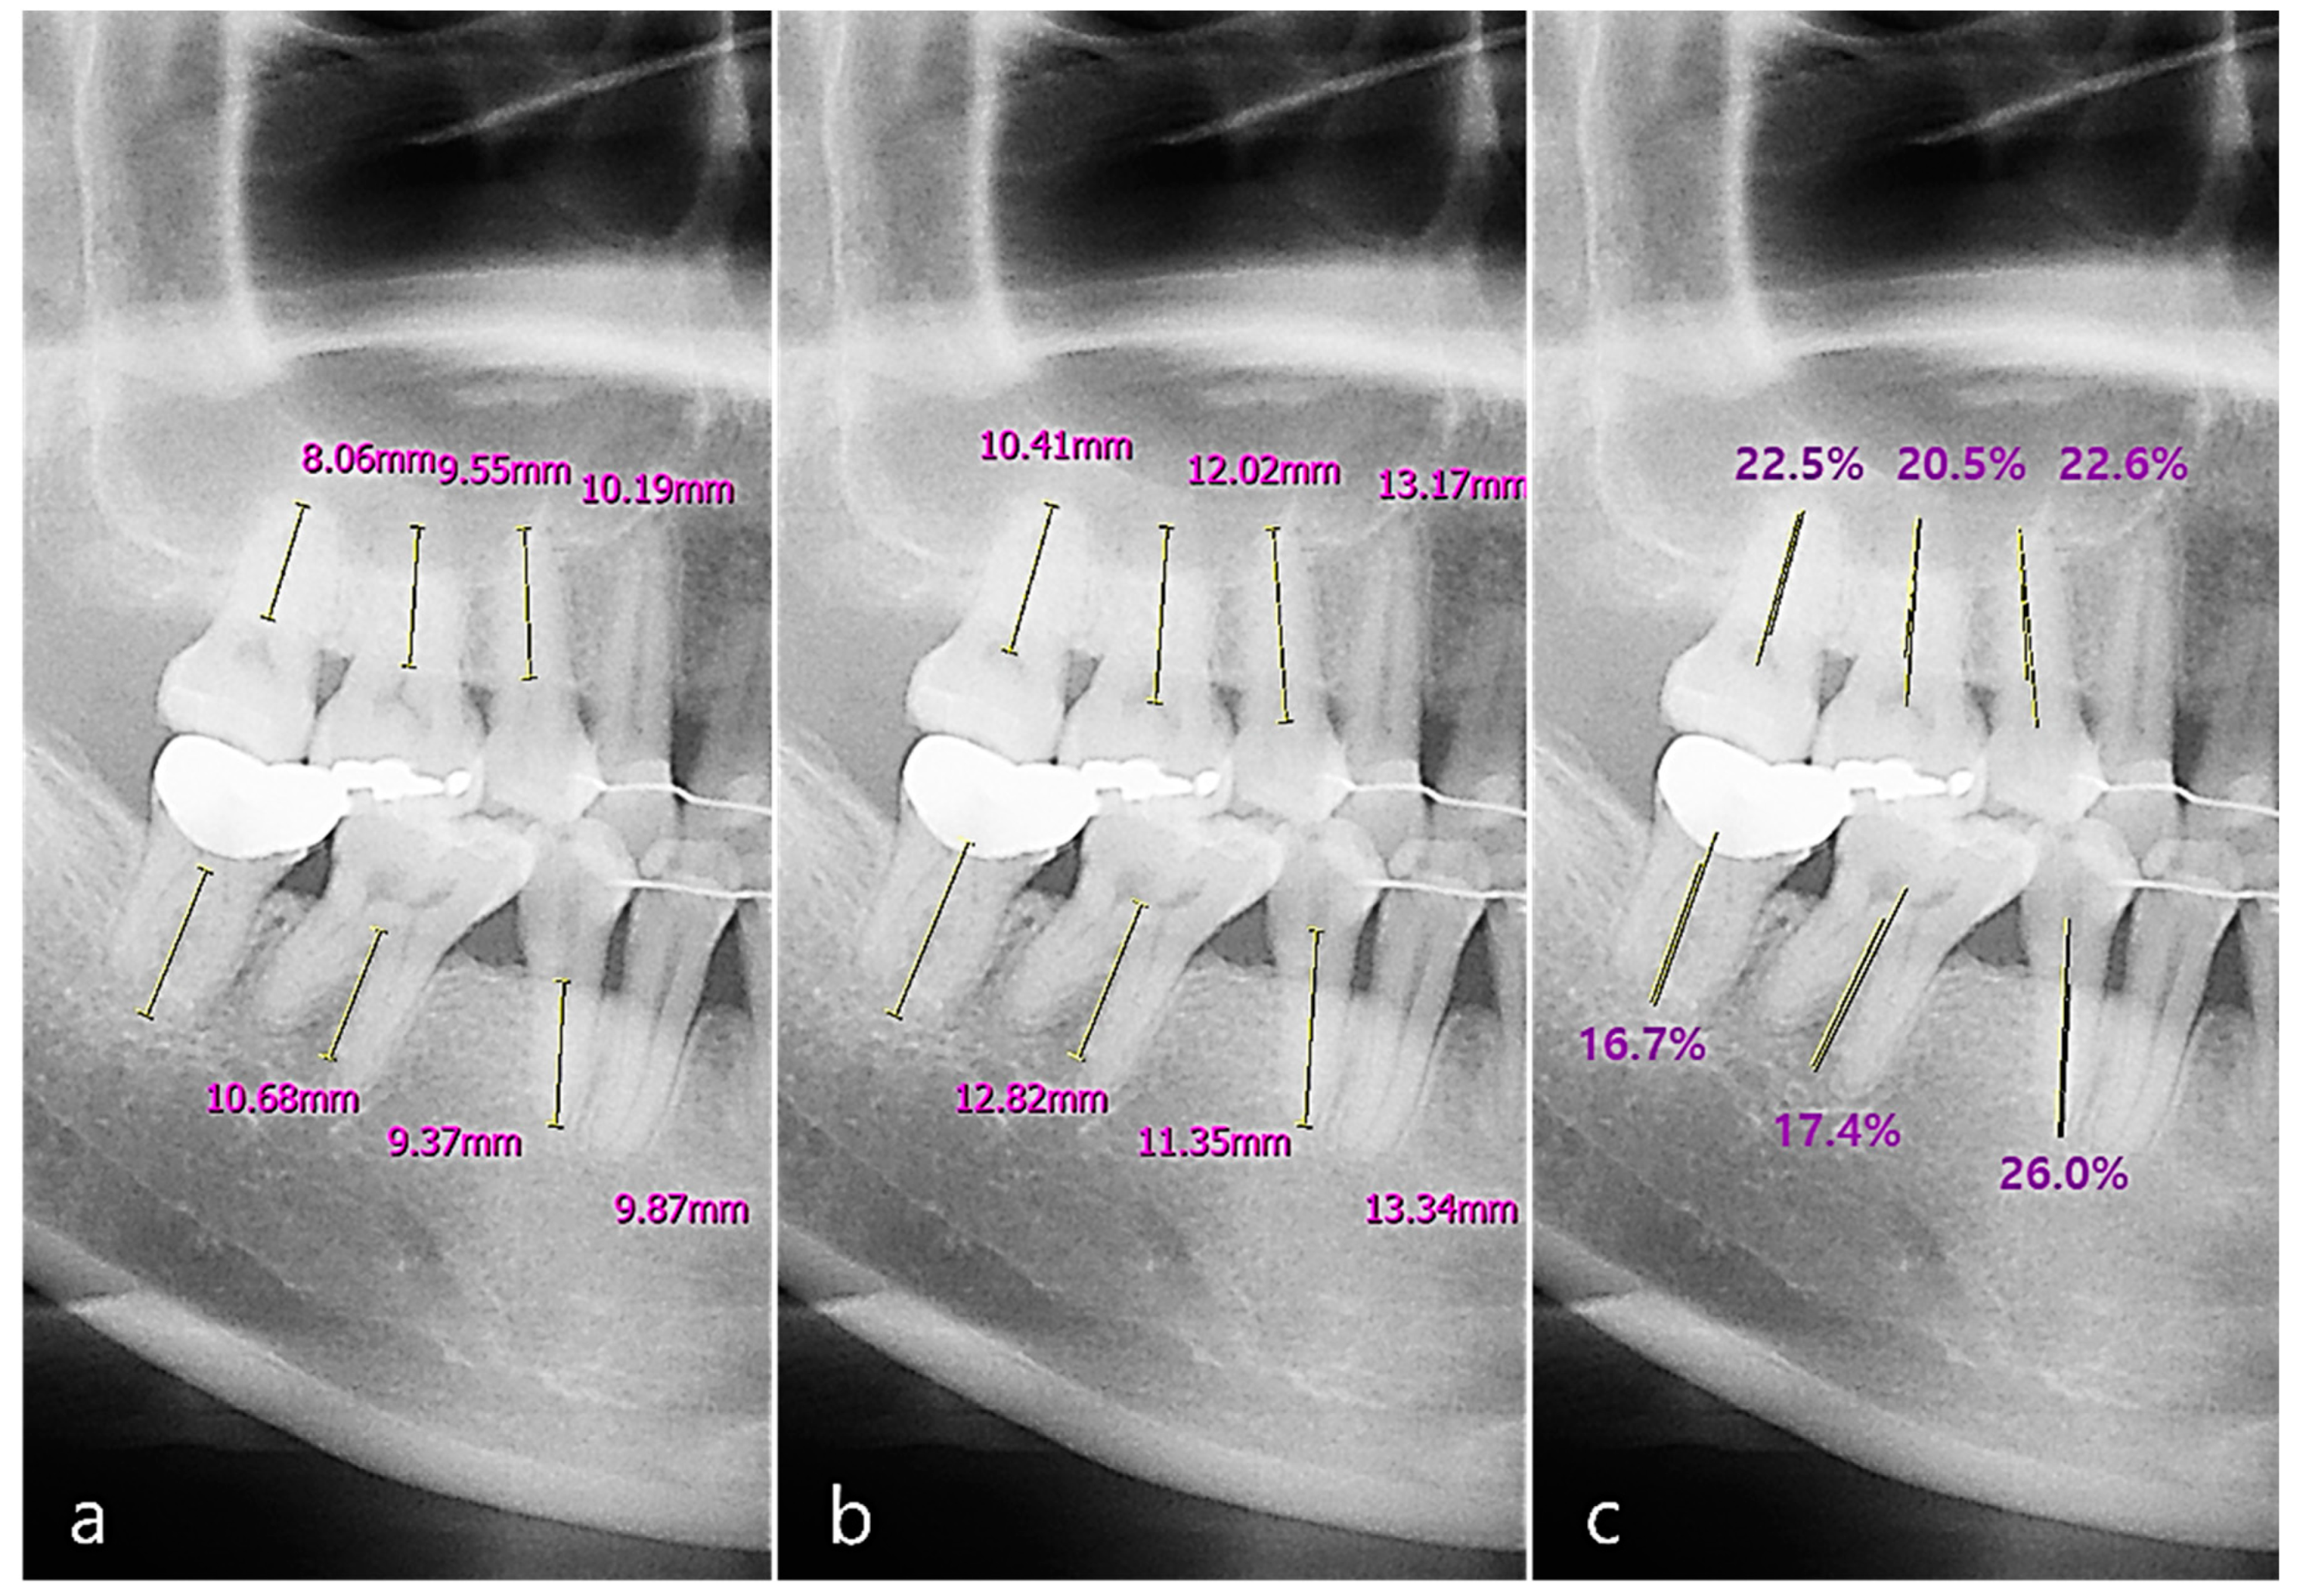

We used 232 image sets, including both panoramic and periapical images, to detect the periodontal bone level (PBL) and cementoenamel junction level (CEJL) of the teeth. We calculated the two tooth intersection lengths as the distances between the points and the root apex of the tooth. We defined the RBL percentage of the tooth (implant) as the ratio of the intersection length of the periodontal bone level to the CEJ (or the top fixture level for an implant) (Figure 5).

Figure 5.

The measurement of RBL (radiographic bone loss) on a panoramic image: (a) the distance from the root tip of the tooth to the periodontal bone level (PBL); (b) the distance from the root tip of the tooth to the cementoenamel junction level (CEJL); (c) the percentage rate of the intersection length of the PBL and the other CEJL.